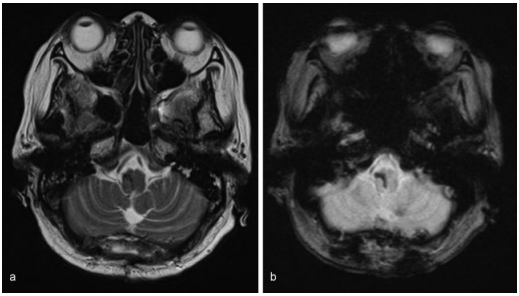

因此,她在入院后3天通过枕下中线入路以半坐位进行手术。枕下开颅术后,大脑池被打开收窄扁桃体和蚓部小舌。在右侧延髓观察到血肿,并通过冲洗清除血肿。血肿清除后,延髓肿胀减轻。术中神经生理监测(运动诱发电位和感觉诱发电位)保持不变。术中无海绵状畸形等病理学证据。术后CT显示血肿完全清除。手术后,她的自主呼吸提高到每分钟15次以上。术后5天停止呼吸机支持,术后6天拔管。术后5周核磁共振成像显示无结构异常。康复后,自主步行出院,没有进一步的并发症。

图:术后5周磁共振成像未见结构异常。